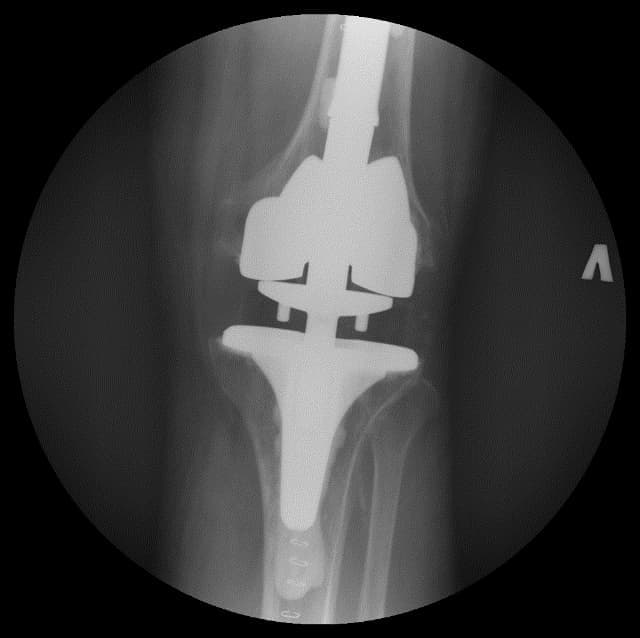

Үе дайрсан ясны анхдагч хавдар, ясны дутмагшлын үед хийгдэх мэс засалimg15Үе дайрсан ясны анхдагч хавдар, ясны дутмагшлын үед хийгдэх мэс засалimg16

Зураг 3. Мэс заслын дараах рентген зураг. Эгц урд, хажуугаас авсан байдал

Өвдөгний үений шөрмөсөн холбоосууд үрэвслийн улмаас бүрэн гэмтсэн Дунд чөмөг - шилбэ ясны 3 зэргийн дутмагшилтай учир дунд чөмөг-өвдөгний хавдрын протез сонгон суулгасан. Энэ дунд чөмөг-өвдөгний хавдрын протезын онцлог нь шилбэ болон дунд чөмөгний хэсэг нь хоорондоо давхар холбогдох нугас буюу hinge system-тэй юм. Hinge system нь үений холбоосын үүргийг гүйцэтгэн – үе хоорондын зайг барих, үений тогтвортой байдлыг хангах зорилготой.